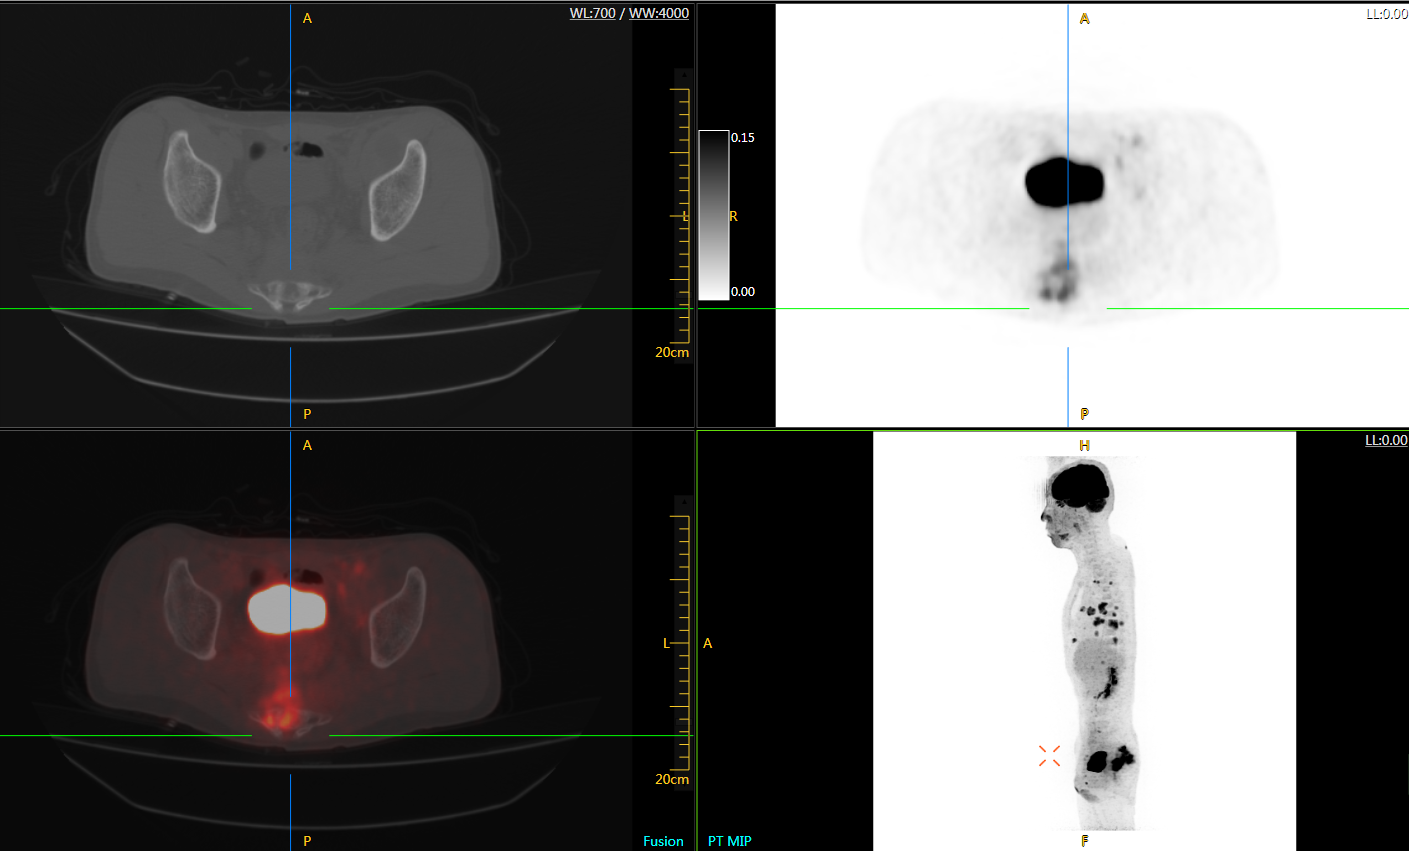

圖例

uExplorer探索者不再局限于傳統(tǒng)靜態(tài)代謝過程3D成像,而是在此基礎(chǔ)上新增一個(gè)維度——時(shí)間,從而實(shí)現(xiàn)4D全景成像。

注射總劑量為7.8mCi,14分鐘全身采集時(shí)間,在擁有超高靈敏度與超高分辨率的uEXPLORER上,即可得到展示顯示人體諸多精細(xì)結(jié)構(gòu)的高清三維圖像。

注射總劑量為7.8mCi,注射后1.6小時(shí),基于uEXPLORER探索者掃描1分鐘的圖像

注射總劑量為0.67 mCi FDG(低于常規(guī)劑量的十分之一),基于uEXPLORER探索者掃描15分鐘的圖像

注射總劑量為6.9mCi,注射后10小時(shí),基于uEXPLORER探索者掃描14分鐘的圖像